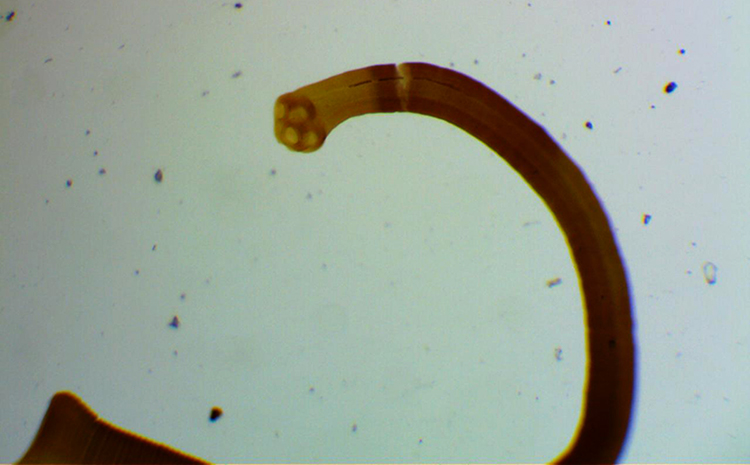

Паразитический червь крысиного цепня (Hymenolepis diminuta) принадлежит к семейству Hymelnolepididae и имеет плоское тело.

Гельминт — это узкий плоский червь, чья длина составляет от 10 до 60,5 сантиметров, а ширина — от 2,2 до 4 миллиметров. На головке цепня находится слабо развитый хоботок без крючков и четыре присоски. Тело состоит из множества коротких члеников (проглоттид).